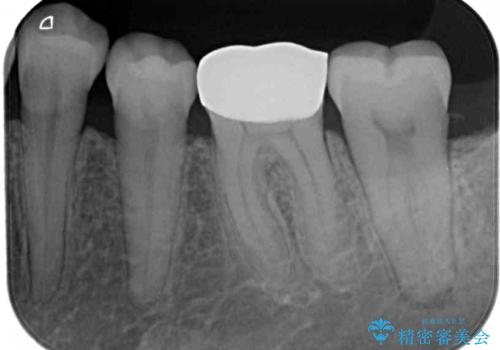

- 人と話す際に、下顎の奥にある銀歯が目立って気になるとのことで来院された患者様です。

左右の奥歯に銀歯のクラウンが装着されていたため、銀歯除去後に仮歯に置き換え、フルジルコニアクラウンにて補綴治療を行うこととしました。